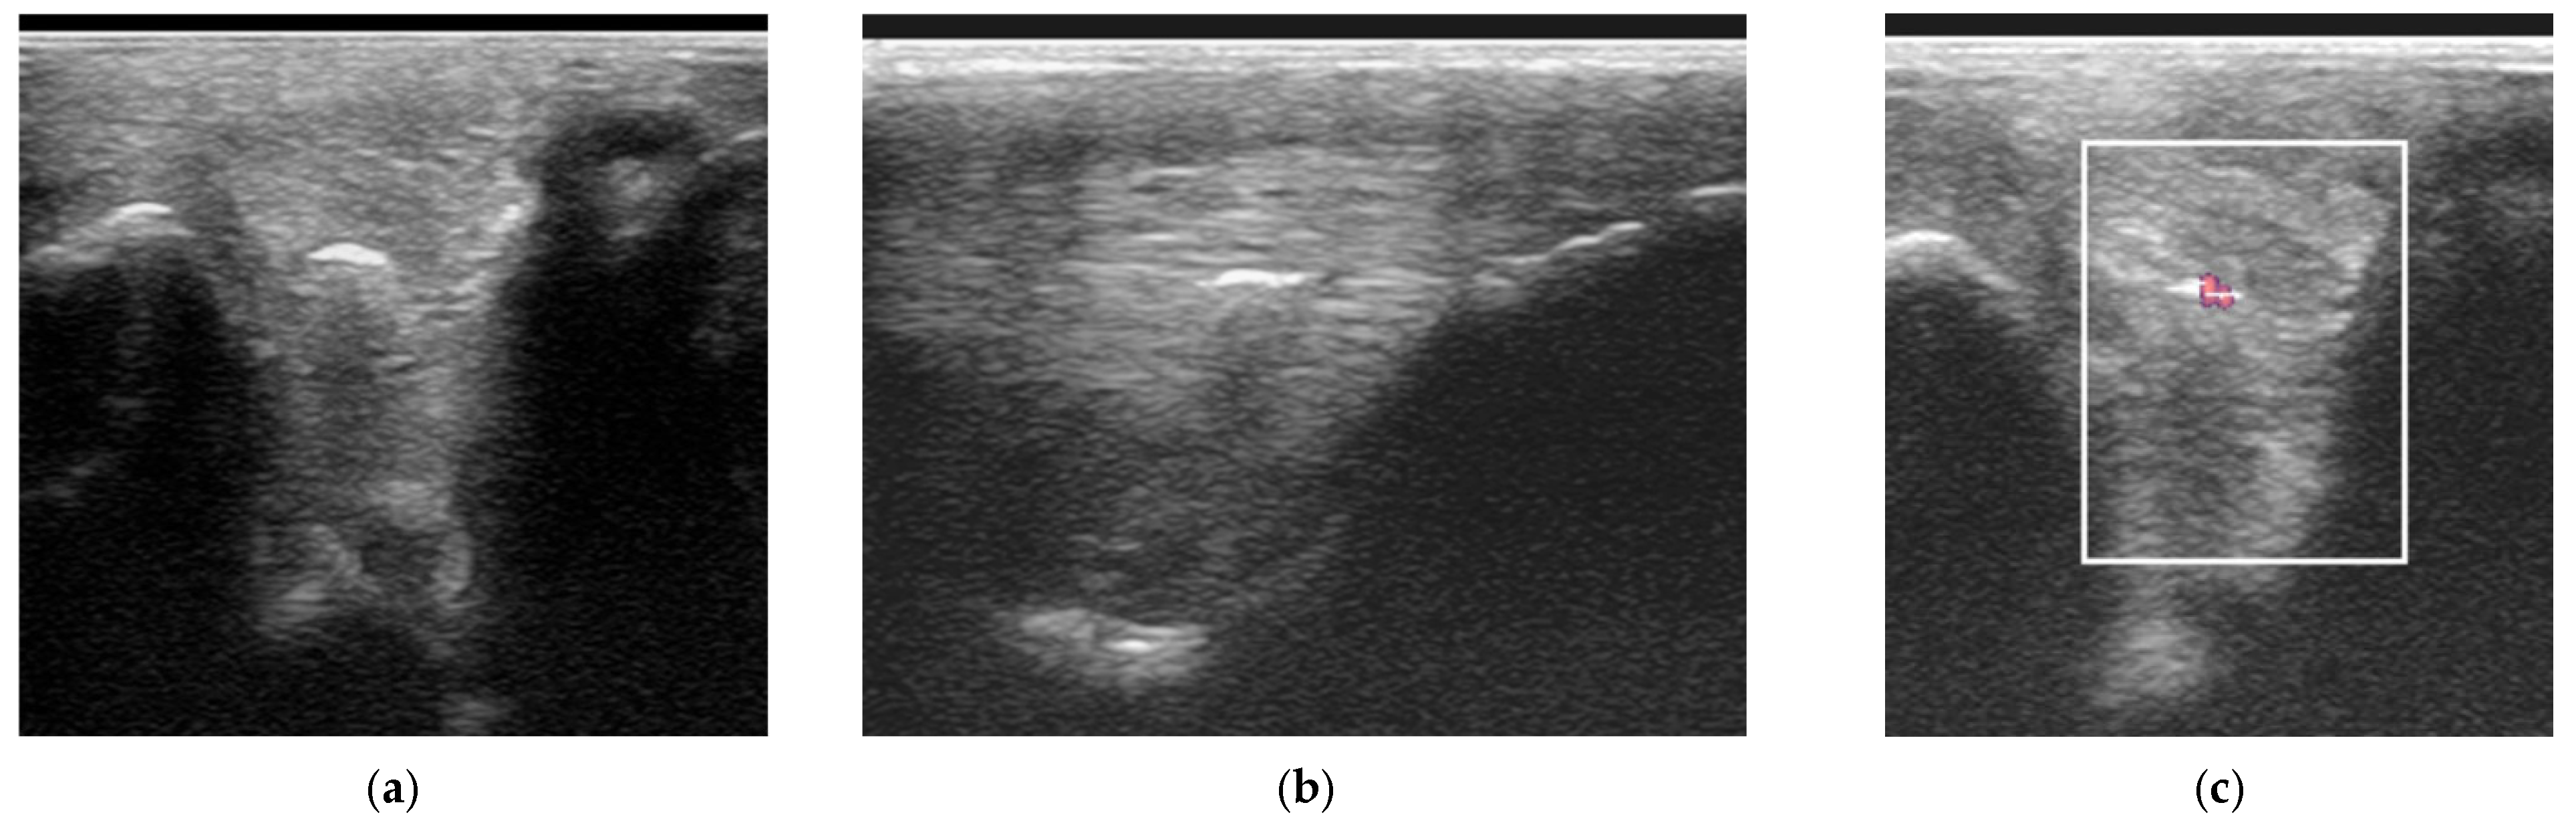

2.3.1. B-Mode Ultrasonography

2.3.2. Power Doppler Examination

2.4.1. Classification of Ultrasonographic Lesions